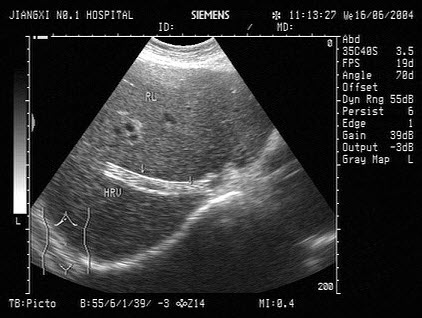

103、单项选择题

男,48岁,上腹胀痛,纳差,血吸虫病多年。结合超声声像图,诊断为()

A.血吸虫肝纤维化